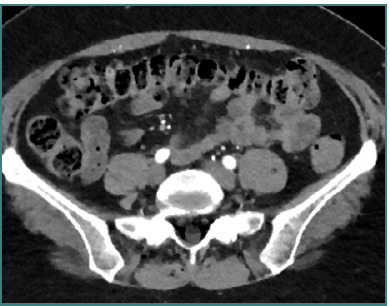

Vascular injuries during anterior lumbar interbody fusion (ALIF) are reported in the existing literature with an incidence rate ranging from 1% to 24%, predominantly venous lacerations owing to branch vessel avulsions during mobilization and retraction. Arterial injuries, although less frequent, occur at an incidence of 0.45% to 1.5% and are mainly characterized by thromboses; aortic lacerations remain exceptionally rare. L4-L5 and L5-S1 are the two levels associated with the majority of vascular complications. Preoperative 3D CT angiography is paramount and a gold standard, as it illustrates the anatomic variations of the iliolumbar vein, the aorta, and the vena cava bifurcation, providing the surgeon with valuable information regarding operative trajectories. Regarding preventive measures, venous laceration, the most common vascular injury, occurs less frequently when employing nonthreaded interbody grafts such as iliac crest autograft or femoral ring allograft. Also, left iliac artery thrombosis can be decreased intraoperatively by intermittent release of retraction. Managing vascular complications includes compression for bleeding control, Trendeleburg positioning of the patient and venorrhaphy, and the employment of topical clot-forming enhancement and/or hemostatic agents. Although postoperative lower limb duplex ultrasonography can be an effective tool, magnetic resonance venography (MRV) and intravenous catheterization (IVC) remain the gold standards for diagnosing postoperative pelvic vein thrombosis in cases of iliac vein repair after anterior spine surgery. This paper aimed to highlight the incidence of major vascular injury during ALIF surgery, describe predisposing risk factors, and discuss management techniques while highlighting the requirement for more sensitive and factor-specific studies to attain a more profound understanding of the mechanism of vasculature complications during ALIF procedures.